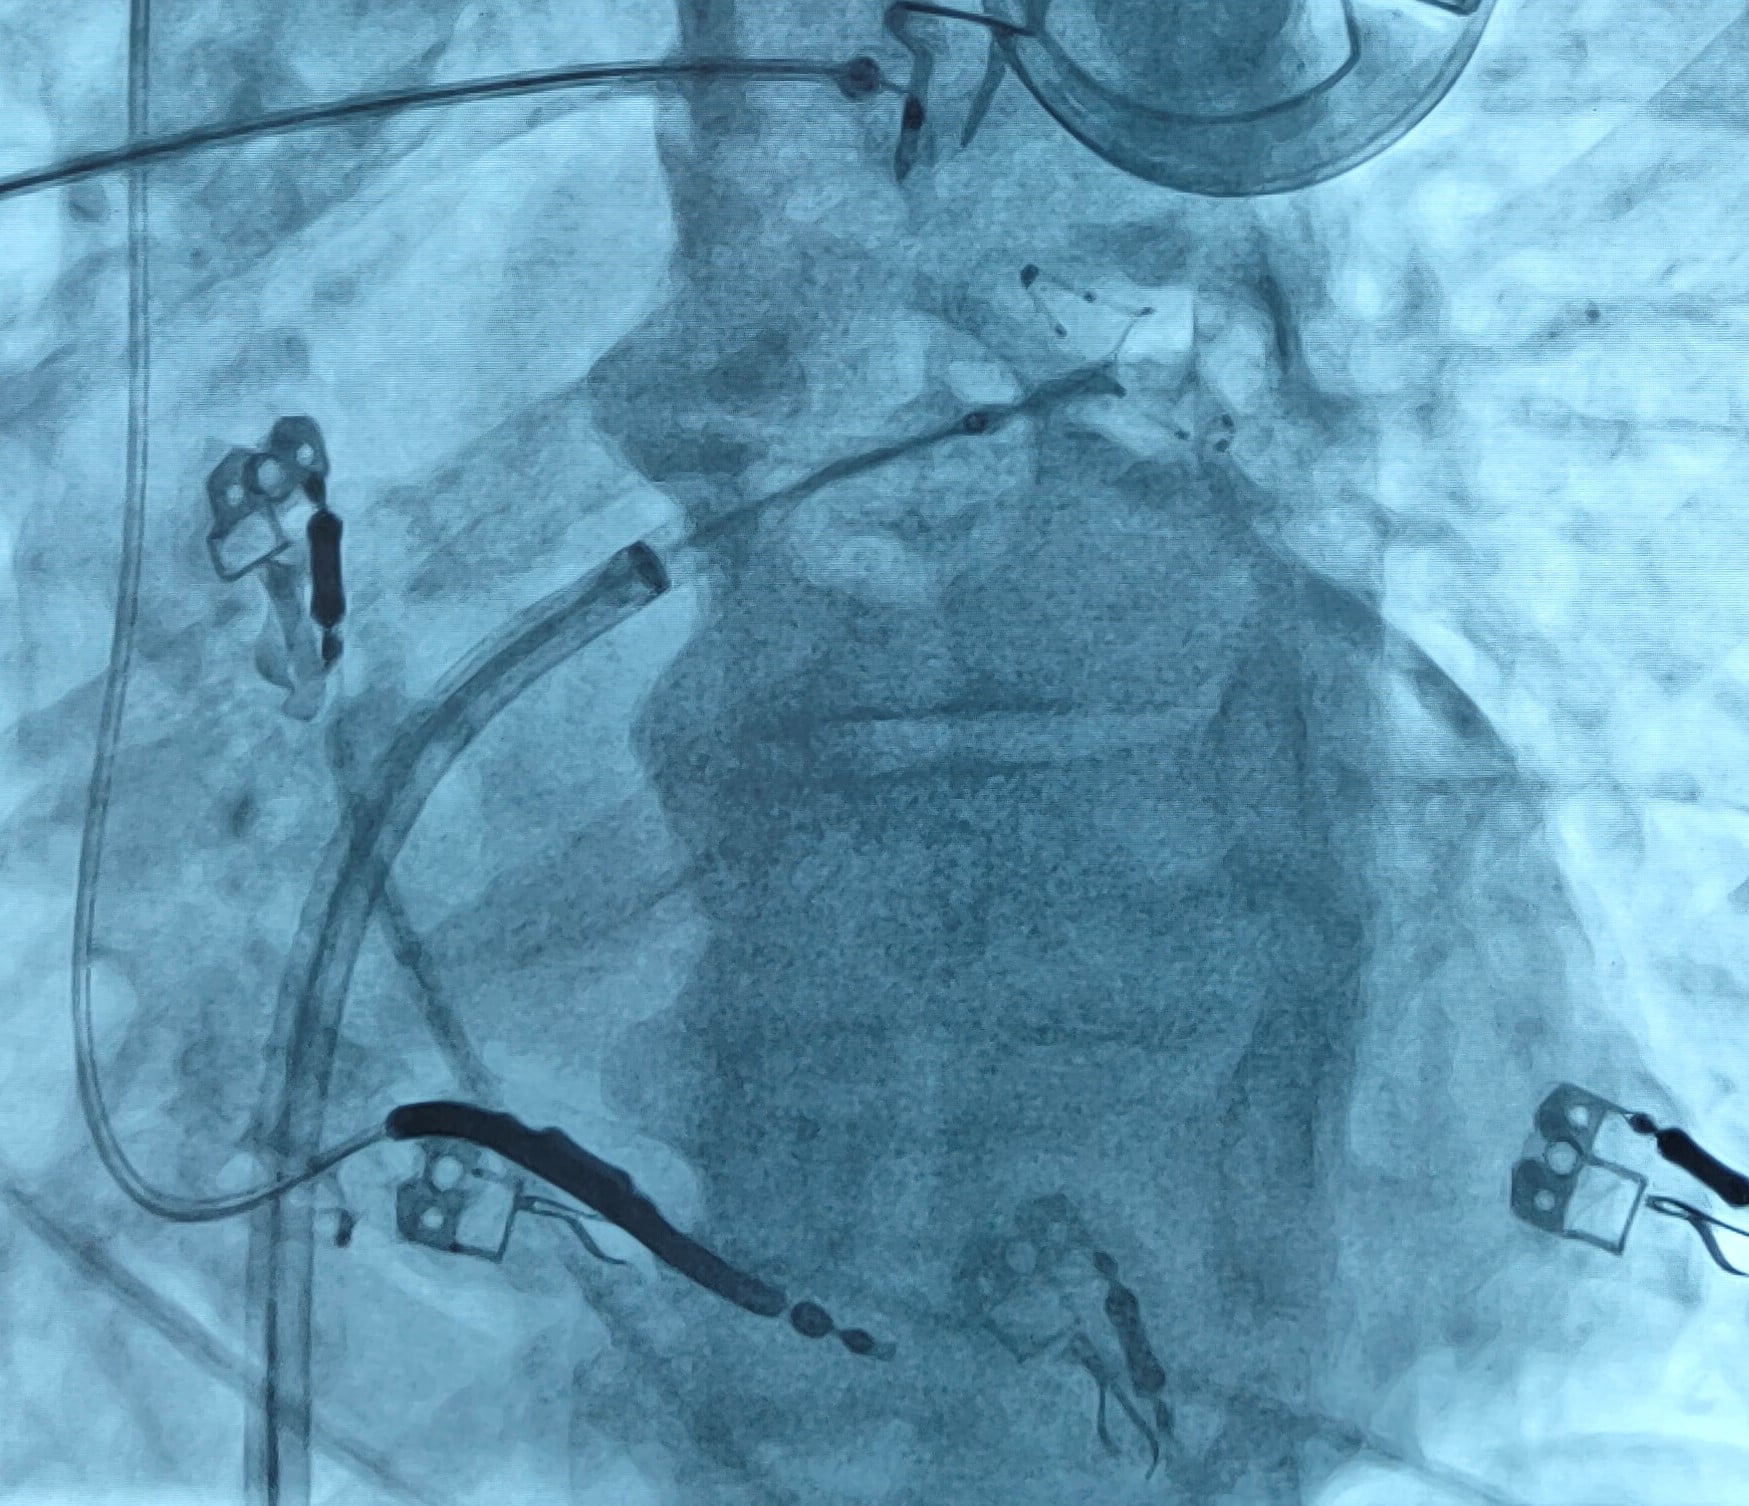

U chorego z implantowanym przedsionkowym regulatorem przepływu przeprowadzono zabieg krioablacji balonowej żył płucnych. Przyczynia się on do zmniejszenia incydentów objawowej arytmii i do zmniejszenia śmiertelności i konieczności hospitalizacji.

Zabieg przeprowadza się metodą krioablacji balonowej lub z wykorzystaniem prądu o częstotliwości radiowej. W obu przypadkach niezbędne jest wykonanie punkcji transseptalnej umożliwiającej wprowadzenie do lewego przedsionka elektrod ablacyjnych.

– U chorego z implantowanym przedsionkowym regulatorem przepływu można ten etap zabiegu ominąć i wprowadzić balon do krioablacji bezpośrednio przez otwór w implantowanym urządzeniu. Skraca to czas trwania procedury i pozwala uniknąć ryzyka związanego z punkcją transseptalną - zauważa dr Adam Priebe, kierownik Pracowni Elektrofizjologii KCCSiN.

Opisywany zabieg był kolejnym już przezskórnym zabiegiem przeprowadzonym u chorego z implantowanym przedsionkowym regulatorem przepływu. Wcześniej, wykorzystując ten specyficzny dostęp, wykonano zabieg ablacji arytmii komorowej oraz implantacji okludera uszka lewego przedsionka.